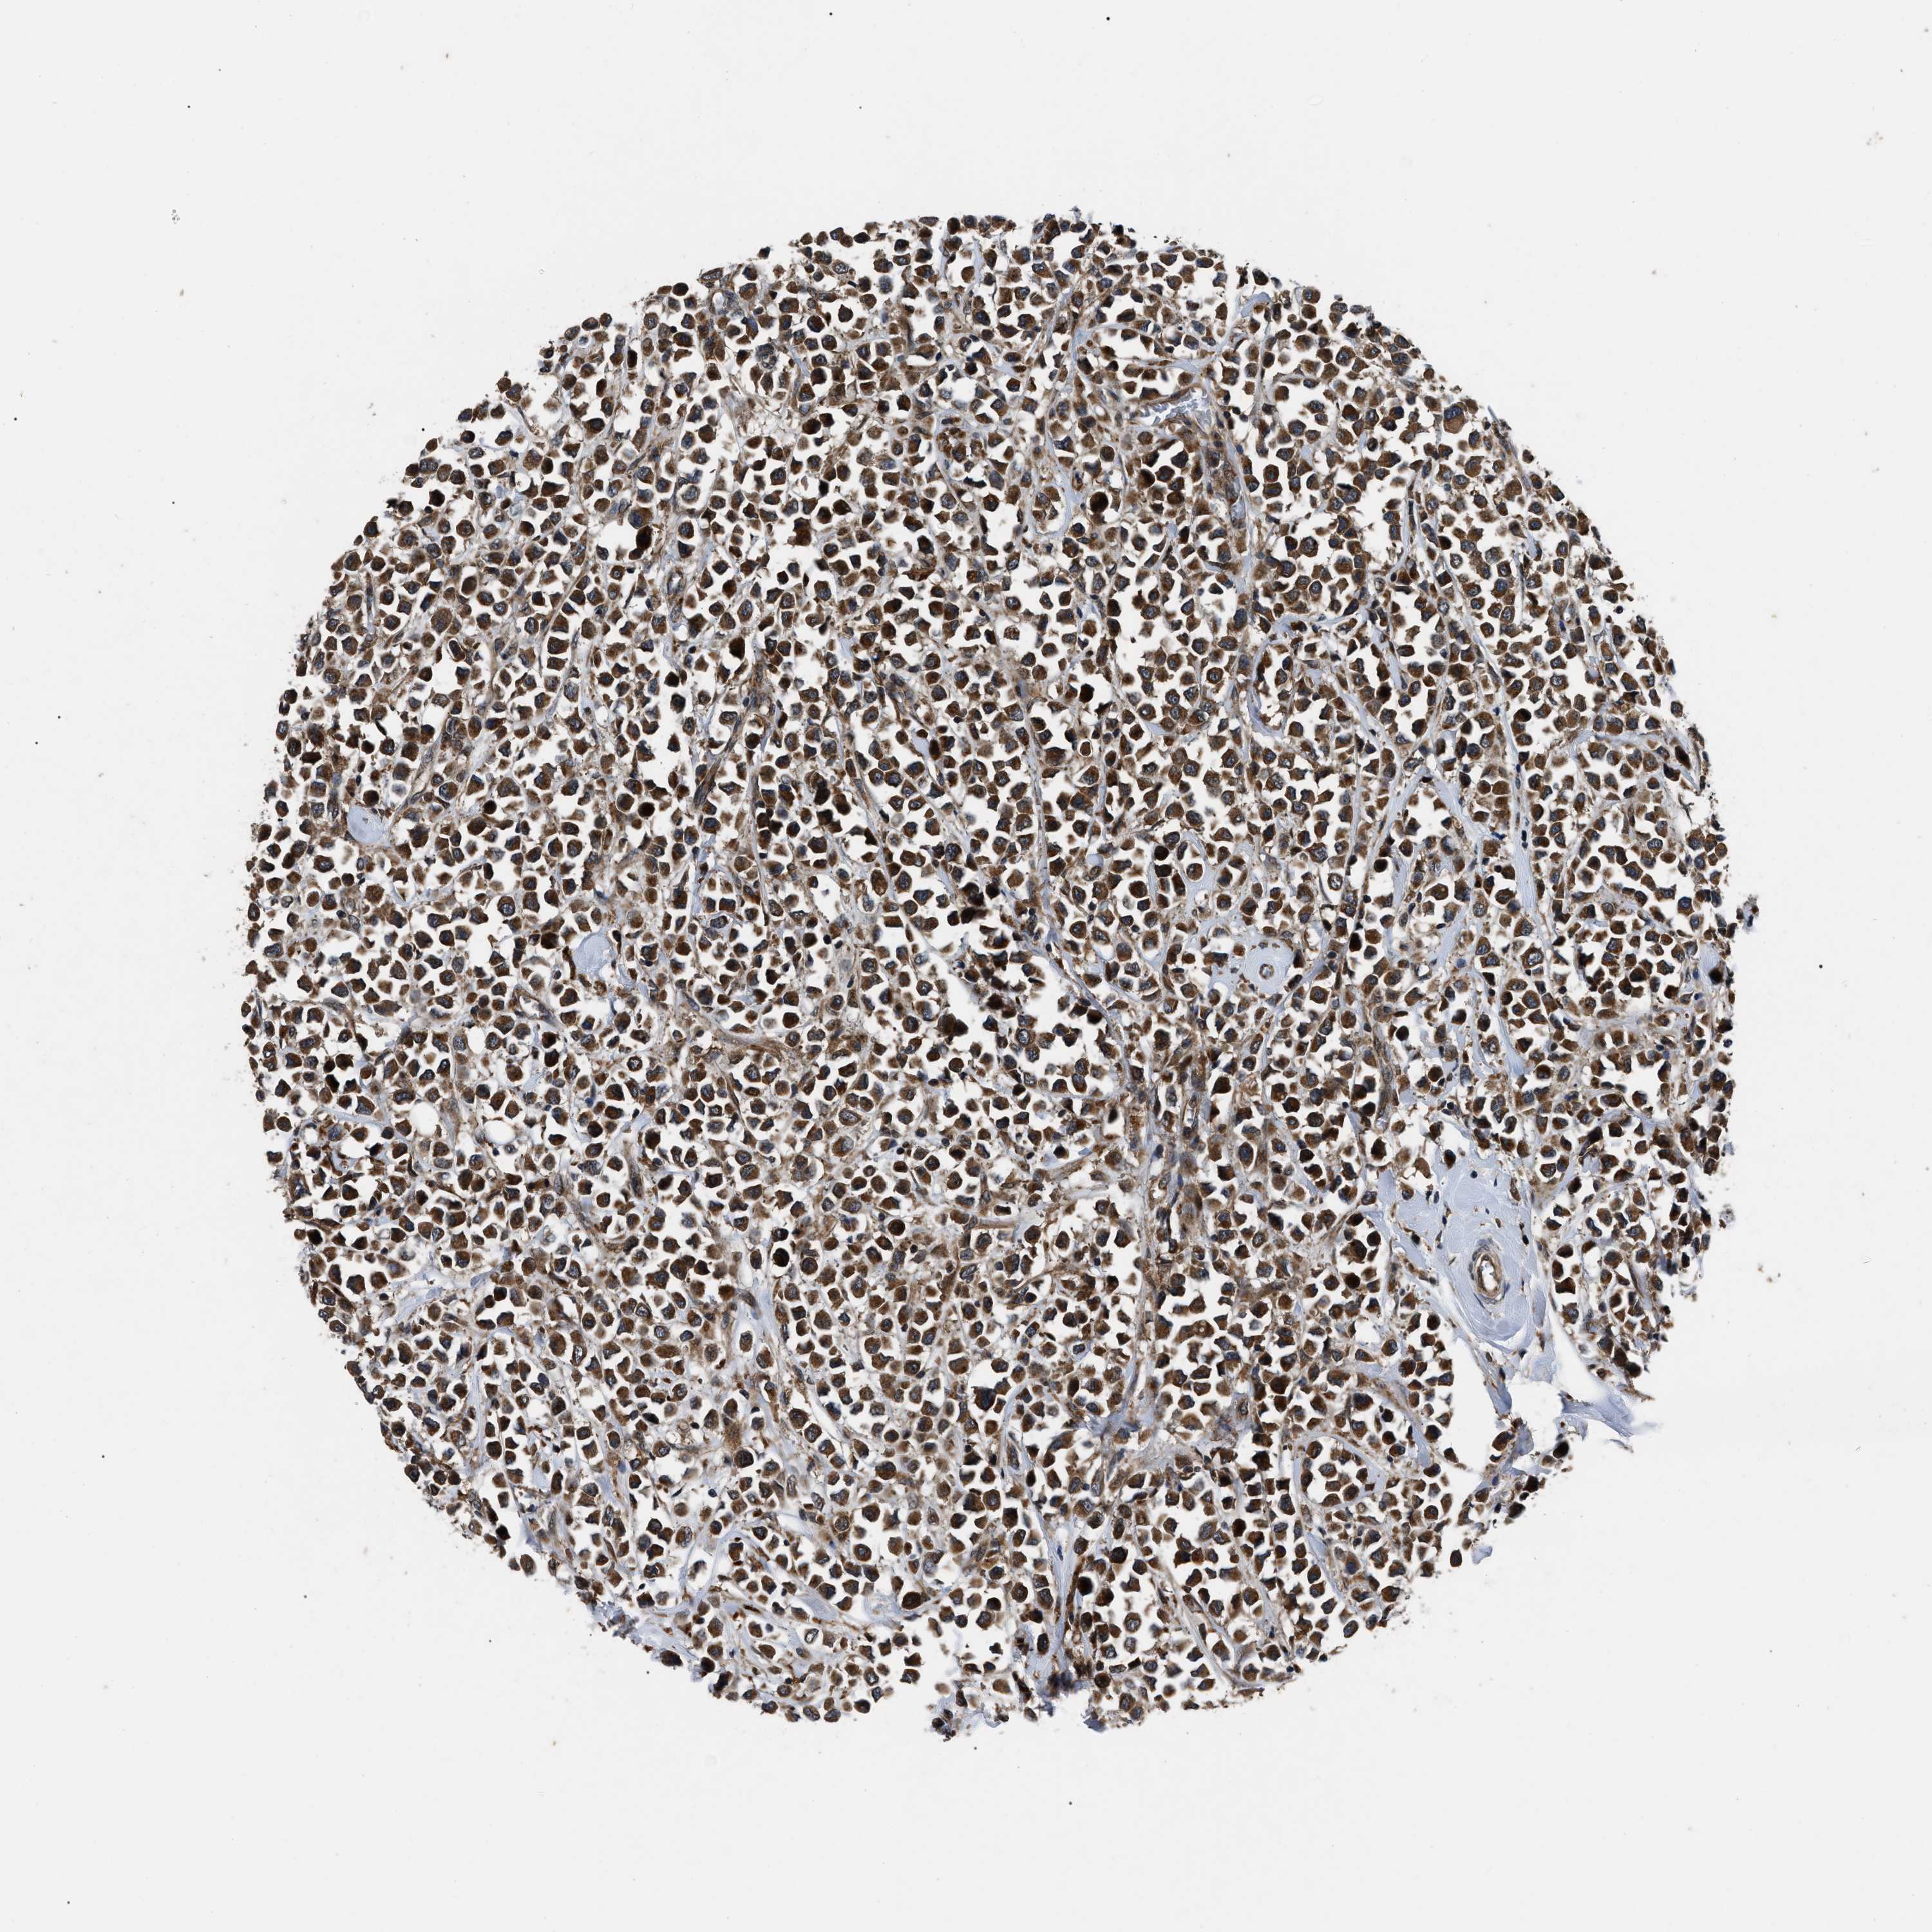

CANCER BREAST CANCER Show tissue menu

BRCA TCGA BRCA VALIDATION PROTEIN EXPRESSION